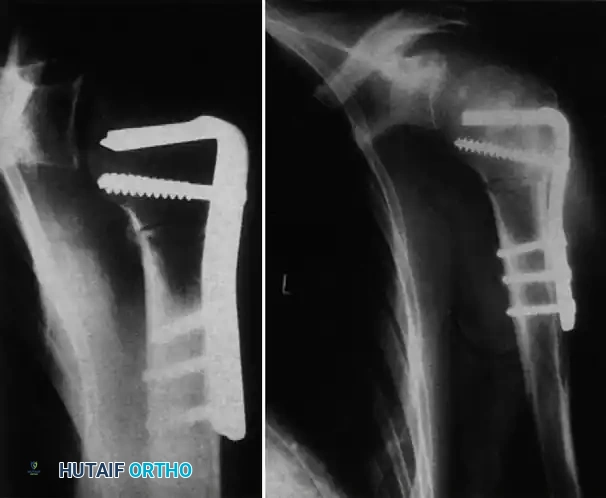

Advanced Reconstruction and Arthroplasty

In cases where the humeral head is non-salvageable (defect >45%, duration >6 months, or severe avascular necrosis), prosthetic replacement is required. Depending on glenoid bone stock, this may involve a hemiarthroplasty or a total shoulder arthroplasty. In cases complicated by severe proximal humerus fractures or nonunions associated with the dislocation, rigid internal fixation with locking plates may be required as a salvage procedure before or in conjunction with joint reconstruction.

Methods of Postoperative Fixation and Immobilization

Maintaining reduction postoperatively is as critical as the reduction itself. Several techniques have been described to prevent early re-dislocation:

1. Transarticular Fixation:

Neviaser recommended transfixing the glenohumeral joint with a Swiss screw to provide rigid temporary stability.

Alternatively, Wilson and McKeever described the use of crossed Kirschner wires driven through the acromion directly into the humeral head.

If internal fixation (screws or K-wires) is utilized, the arm is supported in an abduction splint or spica cast, and the hardware is removed at 3 to 4 weeks in the clinic.